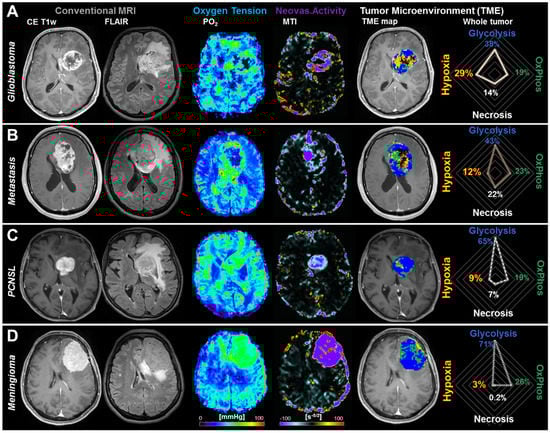

2.2. Physiological MRI and TME Mapping of Contrast-Enhancing Brain Tumors

- Hypoxia without neovascularization or with dysfunctional tumor vasculature for voxels with high OEF, normal CMRO2 (associated with a low PO2 accordingly to Equation (4)), and low MTI: Red diamonds in the OEF-CMRO2-scatterplot and red voxels in the TME map (right-hand side in Figure 3).

- Hypoxia combined with neovascularization activity for voxels with normal to low OEF, high CMRO2 (associated with a low PO2), and high MTI: yellow diamonds in the OEF-CMRO2-scatterplot and yellow voxels in the TME map (right-hand side in Figure 3).

- Necrosis for voxels with very low CMRO2 and high OEF combined with highly defective tumor vasculature: Black crosses in the OEF-CMRO2-scatterplot and black voxels in the TME map (right-hand side in Figure 3).

- OxPhos for voxels with normal to low OEF, high CMRO2 (associated with normal PO2), and functional tumor neovasculature, under the assumption of predominantly mitochondrial oxidative phosphorylation for energy production: Green squares in the OEF-CMRO2-scatterplot and green voxels in the TME map (right-hand side in Figure 3).

- Glycolysis for voxels with low OEF, low CMRO2, (associated with high PO2), and functional tumor neovasculature, under the assumption of predominantly cytosolic aerobe glycolysis by the Warburg effect for energy production: Blue circles in the OEF-CMRO2-scatterplot and blue voxels in the TME map (right-hand side in Figure 3).

| Glioblastoma | Metastasis | PCNSL | Meningioma | |

|---|---|---|---|---|

| Aerobic Glycolysis | 37% ± 22% 1–70% | 48% ± 25% 18–86% | 59% ± 10% 47–77% | 63% ± 27% 22–94% |

| Oxidative Phosphorylation | 17% ± 6% 1–27% | 26% ± 17% 5–53% | 22% ± 4% 18–28% | 26% ± 22% 2–53% |

| Vital Tumor | 54% ± 24% 7–90% | 74% ± 18% 44–95% | 81% ± 10% 66–96% | 90% ± 9% 75–99% |

| Necrosis | 22% ± 11% 3–44% | 19% ± 17% 3–47% | 11% ± 8% 2–25% | 3% ± 3% 0–8% |

| Hypoxia with Neovascularization | 15% ± 10% 0–36% | 5% ± 4% 0–14% | 5% ± 4% 0–11% | 7% ± 7% 1–18% |

| Hypoxia without Neovascularization | 9% ± 7% 0–27% | 2% ± 2% 0–6% | 3% ± 2% 0–6% | 1% ± 1% 0–2% |

| Total Hypoxia | 24% ± 16% 0–52% | 7% ± 5% 1–14% | 8% ± 5% 1–15% | 8% ± 7% 1–20% |